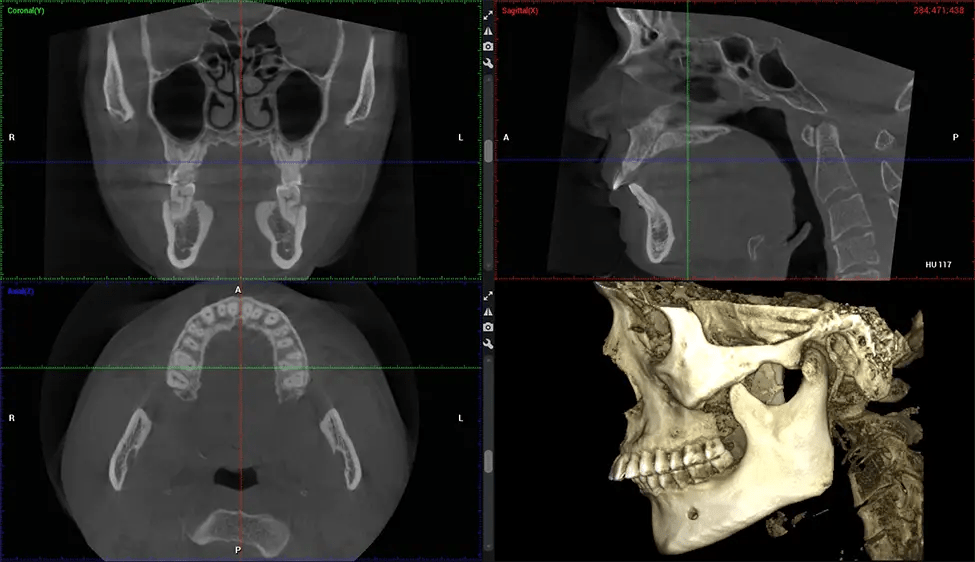

This 3D scan, called cone beam computed tomography, gives your dentist a more complete image of your oral anatomy and disease processes than a traditional X-ray. Unlike conventional X-rays, which capture a 2D image of your mouth from various angles, a 3D scan takes multiple digital X-rays for one image. It provides a complete view of your jaw, teeth, nerves, and soft tissues. This enhanced view allows dentists to detect minor issues not visible in traditional 2D scans, such as impacted wisdom teeth or bone fractures in the sinus cavity.

There are many benefits to using CBCT technology, especially compared to the traditional 2D X-ray format. One of the most significant advantages of CBCT scans is that they provide much more information than traditional X-rays. A scan lets your dentist see images from all angles of your jaw and mouth, including your sinuses, nasal cavity, cheekbones, and other surrounding areas. This added information helps your dentist craft a comprehensive treatment plan that addresses all aspects of your oral health.

Planmeca Viso G7 CBCT ( Cone Beam CT Scan ) is designed to surpass the demands of industry leaders, specialists, and large institutions. It’s has a large ø25×30 cm sensor with four built-in cameras. It can capture unlimited volume sizes from a ø3×3 cm to a ø30x30cm volume capturing the skullcap through C7 on the cervical spine. The Planmeca Viso G7 offers the industry’s largest single volume scan of ø30×19 cm. It’s poised to handle advanced imaging modalities such as Planmeca ProFace® and Planmeca 4D™ Jaw Motion technology. The occipital head support allows an unimpeded view of facial tissue.